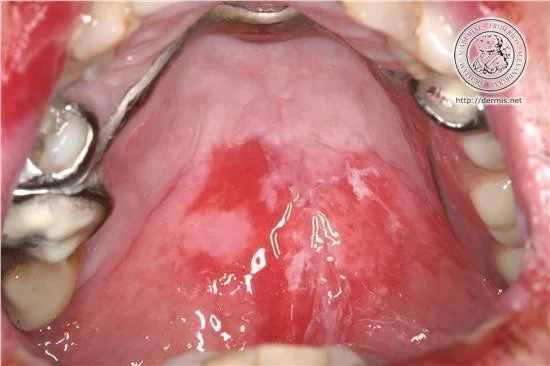

Mucous Membranes

- Almost all patients have mucosal lesions.

- Mucosal lesions may precede the cutaneous lesions by 6 months.

Clinically by flaccid bullae and or erosions in the mucus membranes and skin